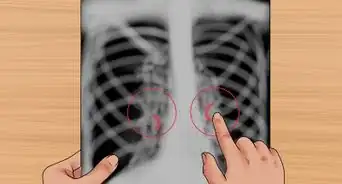

1Know what to expect during a chest X-ray. A chest X-ray is one of the most common X-ray procedures and is used to produce images of the heart, lungs, airways, blood vessels, and the bones of the spine and chest. It's normally used for diagnosing problems such as:[8]

- Shortness of breath, bad or persistent cough, and chest pain or injury.

- It can also be used for diagnosing or monitoring conditions such as pneumonia, heart failure, emphysema, lung cancer, and fluid or air around the lungs.

- If your doctor recommends that you should get a chest X-ray, no special preparation is required – just follow the steps mentioned above.

- A chest X-ray takes about 15 minutes and often requires two views of the chest to be taken.